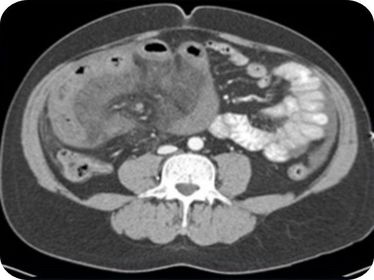

EQUINOCOCOSIS

ISQUEMIA MESENTÉRICA

OBSTRUCCIÓN DEL INTESTINO DELGADO

PSEUDOQUISTES PANCREATICOS

VÓLVULO CECAL